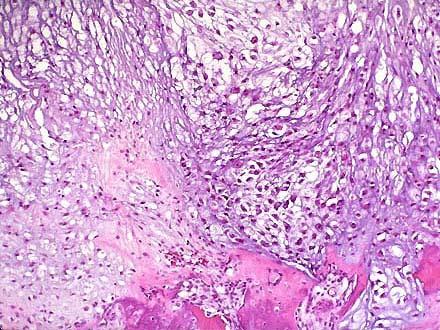

问题 患者,男,56岁,坐骨肿瘤切除,肿瘤位于骨髓腔内,灰白色分叶状,切面可见黄色的钙化和骨化灶。镜下如图1、2所示软骨基质中散布异型软骨细胞。正确的诊断是 ( )

选项 A.软骨瘤 B.软骨肉瘤 C.骨软骨瘤 D.骨肉瘤 E.骨纤维肉瘤

答案 B